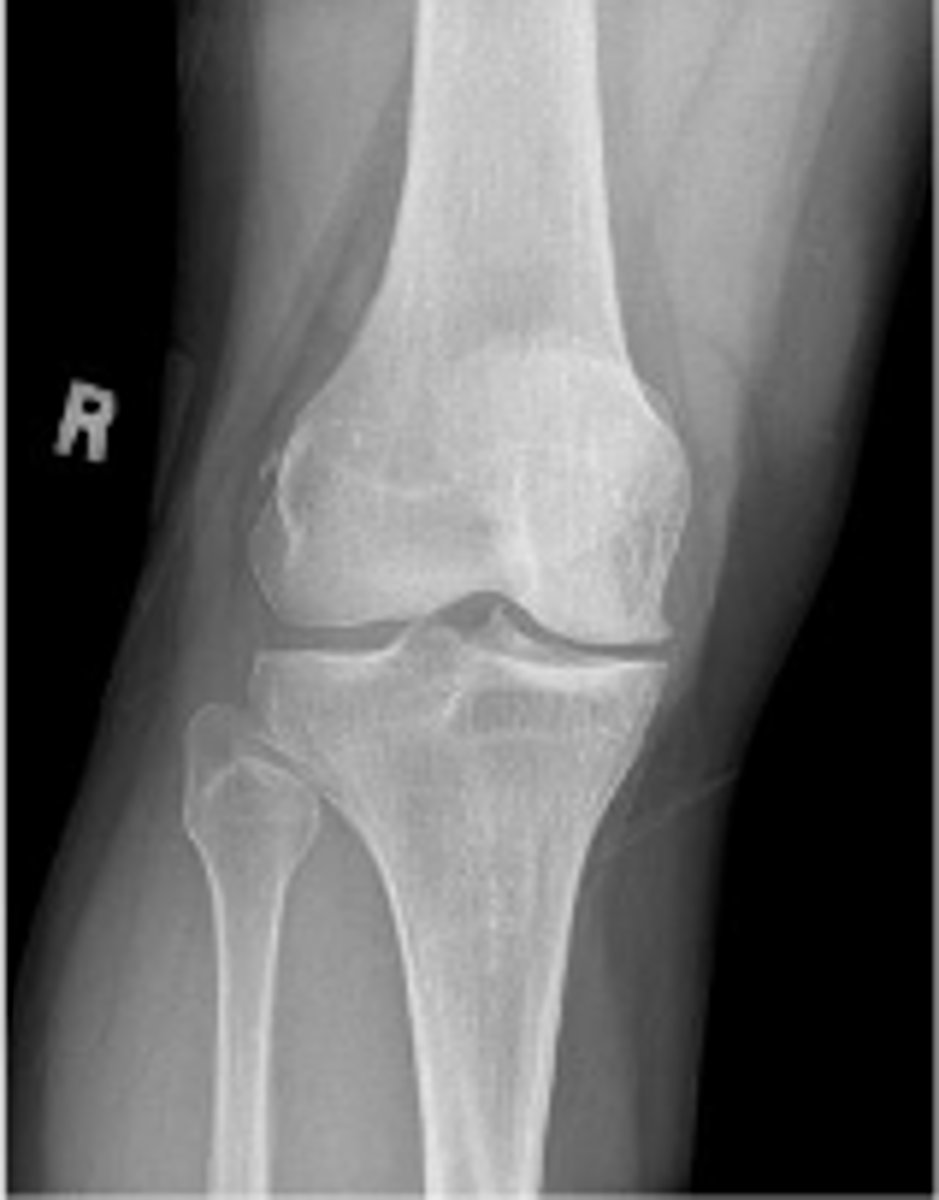

Right internal oblique knee

What is the name of the radiographic view?